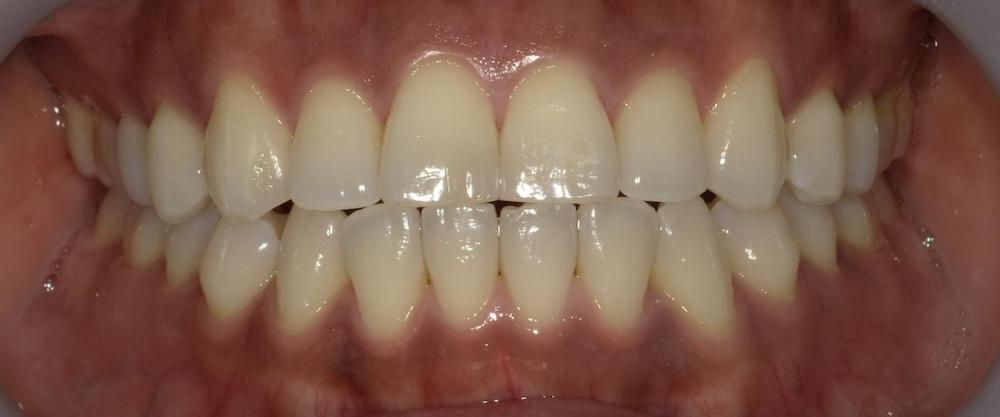

症例2 舌癖による後戻りケース (軽度)

舌を前歯に押し付ける癖があり、徐々に前に出てきてしまったため再矯正を行いました。矯正中から舌トレーニングを行い舌癖の改善に努めました。

- 治療方法 :インビザラインエクスプレス上下

- 治療期間 :6ヶ月

- 治療費用:¥385000(税込)

- 治療のリスク・デメリット :舌癖の改善をする必要がある

Before

After